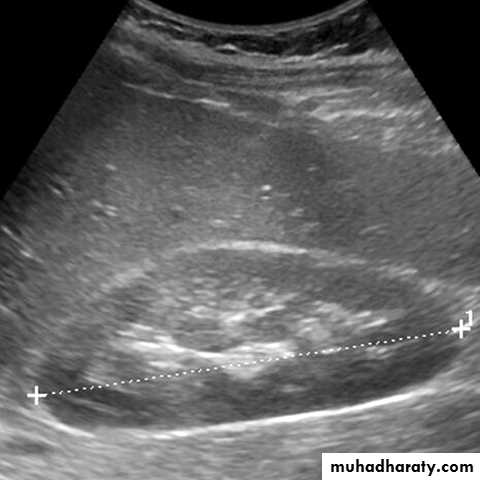

Measurement of renal length by US